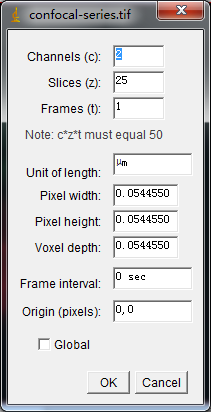

共聚焦图片Z-Stack层扫可以得到Stack或Hyperstacks图片,下图为共聚焦系列图片,该图片包含红、绿两通道以及Z轴25张切片:

图片属性可通过Image -> Properties得到: